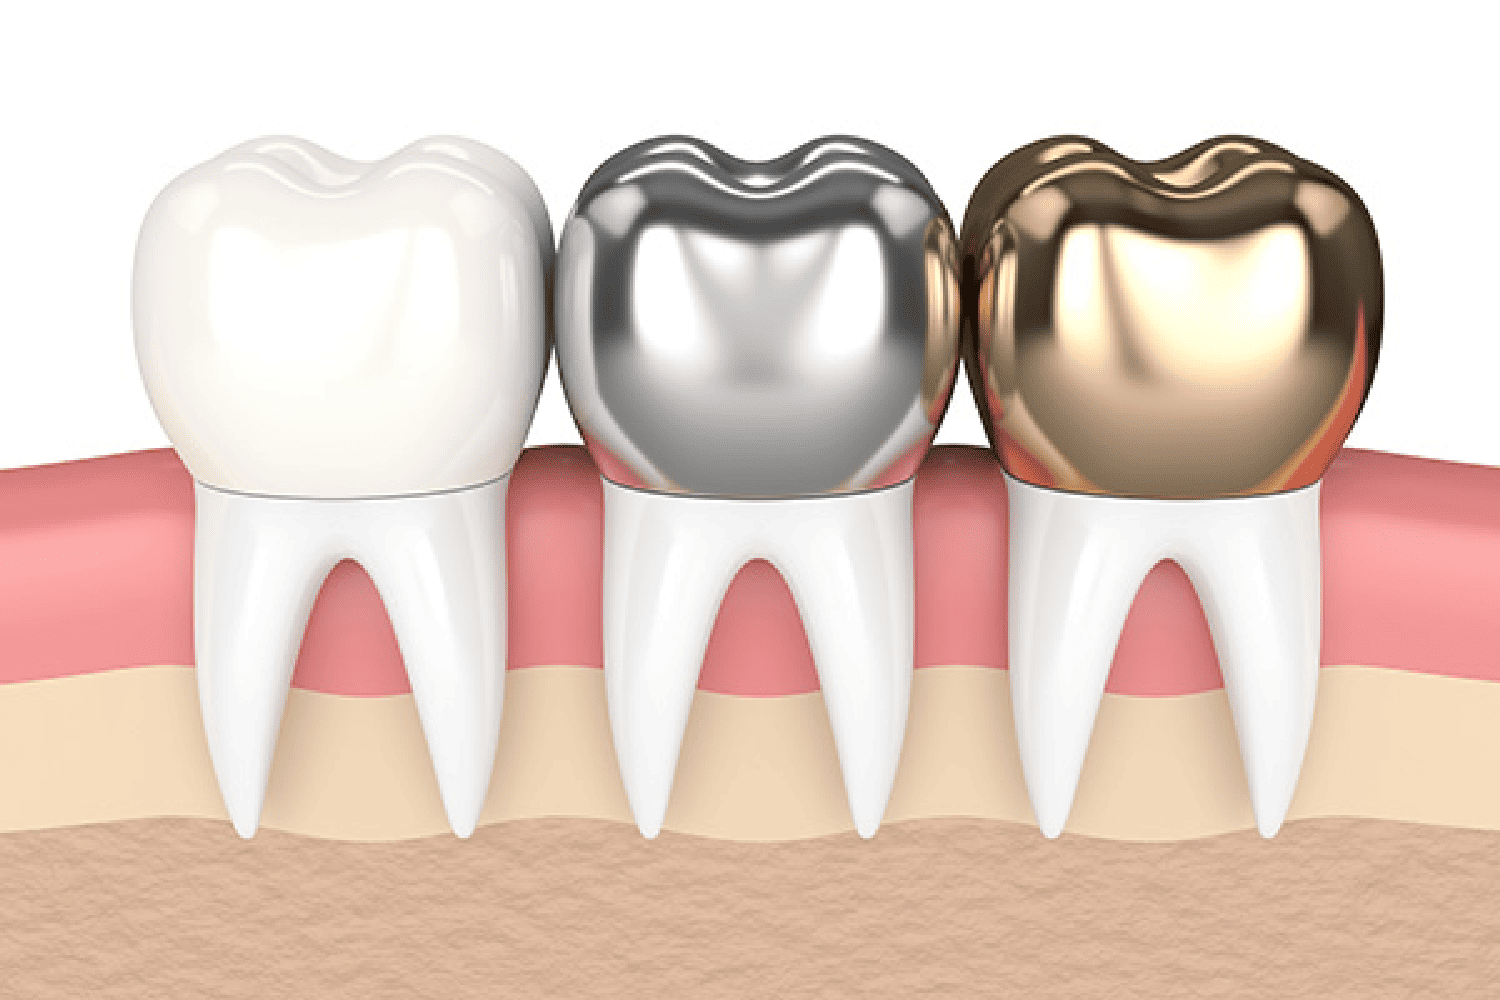

Dental Crowns in Jaipur Services Crowns Bridges Dentures...